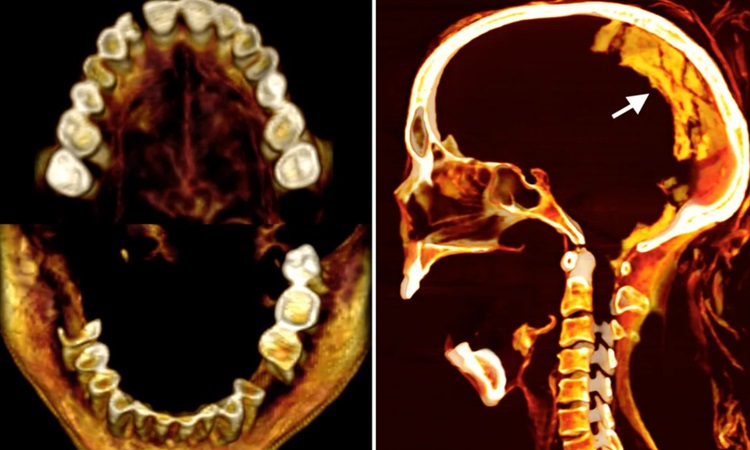

Ảnh chụp cắt cắt lớp khuôn miệng há to của Người phụ nữ hét. Ảnh: Sahar Saleem

Nhưng trường hợp này lại khác. Khuôn miệng há to là kết quả từ cái chết đau đớn. Biểu cảm gương mặt la hét trong nghiên cứu này có thể được xem như dấu hiệu co cứng tử thi, có nghĩa người phụ nữ chết trong lúc la hét vì đau đớn. Co cứng tử thi xảy ra khi cơ bắp co rút ngay trước lúc chết, chiến chúng cứng lại. Tình trạng đó có thể xảy ra trong trường hợp chết do tấn công, tự tử hoặc chết đuối. Không giống nguyên nhân cái chết của hai xác ướp trên (Pentawere tự tử và Meritamun bị đau tim), ảnh chụp cắt lớp vi tính Người phụ nữ hét không thể hiện nguyên nhân cái chết của bà.

Tuy nhiên, ảnh 2D và 3D từ bản chụp cắt lớp giúp làm sáng tỏ chiều cao, độ tuổi và tình trạng sức khỏe của bà. Người phụ nữ cao khoảng 1,5 mét. Khớp giữa hai xương chậu (thay đổi theo tuổi tác) chỉ ra bà khoảng 48 tuổi khi qua đời. Xương ở cột sống cũng cho thấy bà có thể bị viêm khớp nhẹ. Người phụ nữ mất vài chiếc răng, có thể ngay trước khi chết, thể hiện qua ổ răng chưa lành.